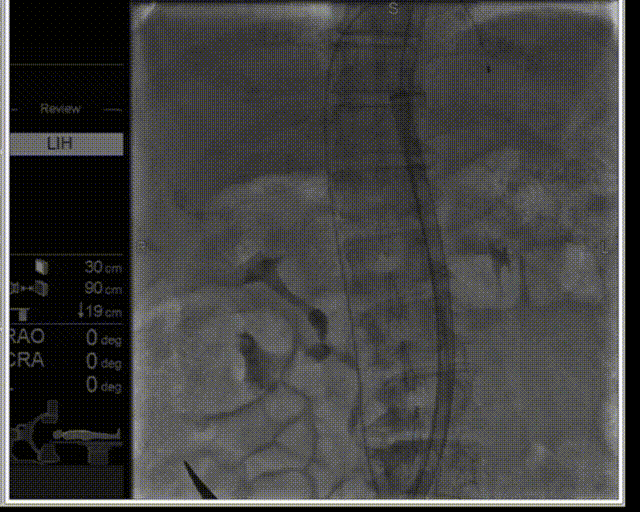

瓣膜释放

髂动脉撤大鞘

超声下血流动力学良好,微量反流